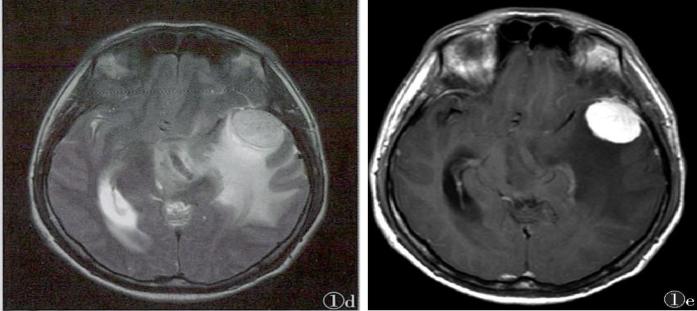

答案:枫糖尿病。枫糖尿病是由α-酮酸脱氢酶多酶复合体功能缺陷引起的常染色体隐性遗传病。婴儿起病的白质脑病要想到枫糖尿病。影像上要注意和Leigh综合征鉴别。Leigh综合征多在10岁以前发病,以婴幼儿多见;神经系统的主要表现为抽搐、卒中发作、眼外肌麻痹、痴呆、共济失调、视神经病变等。Leigh多为双侧对称性分布,病变形态不规则,大小不等,呈斑块状;病变主要累及双侧壳核及导水管周围灰质,也可累及丘脑(尤其是背内侧核)、小脑齿状核、脑干、脑白质和皮质均可受累;MRI呈长T1、长T2信号,T2-FLAIR和DWI像病变信号多不均匀。枫糖尿病特点为弥漫性的脑白质水肿,遍及大脑和小脑半球的TW2I上的高信号,尤其在基底节及脑干区。典型表现为侧脑室旁、基底节区、脑干、小脑T2WI及DWI上的高信号影,DWI显示的更加敏感;MRS在0.9ppm处可发现一个相对特异性的宽峰;同时可见NAA峰的下降及Lac峰的升高。